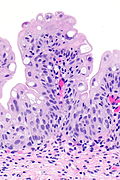

Urothelial papilloma. H&E stain.

LM papillary fronds with minimal branching or fusion, cytology and thickness of normal urothelium, no mitoses

Microscopic

Features:[2]

• Papillary fronds.

• Minimal branching or fusion.

• Cytological features of normal urothelium.

• Normal urothelium approx. 2x the size of stromal lymphocytes.[3]

• No mitoses.

• Thickness < 7 cells.[citation needed]

The sections show superficial fragments of a papillary urothelial lesion. The cytology and thickness is that of normal urothelium. No proliferation is apparent.